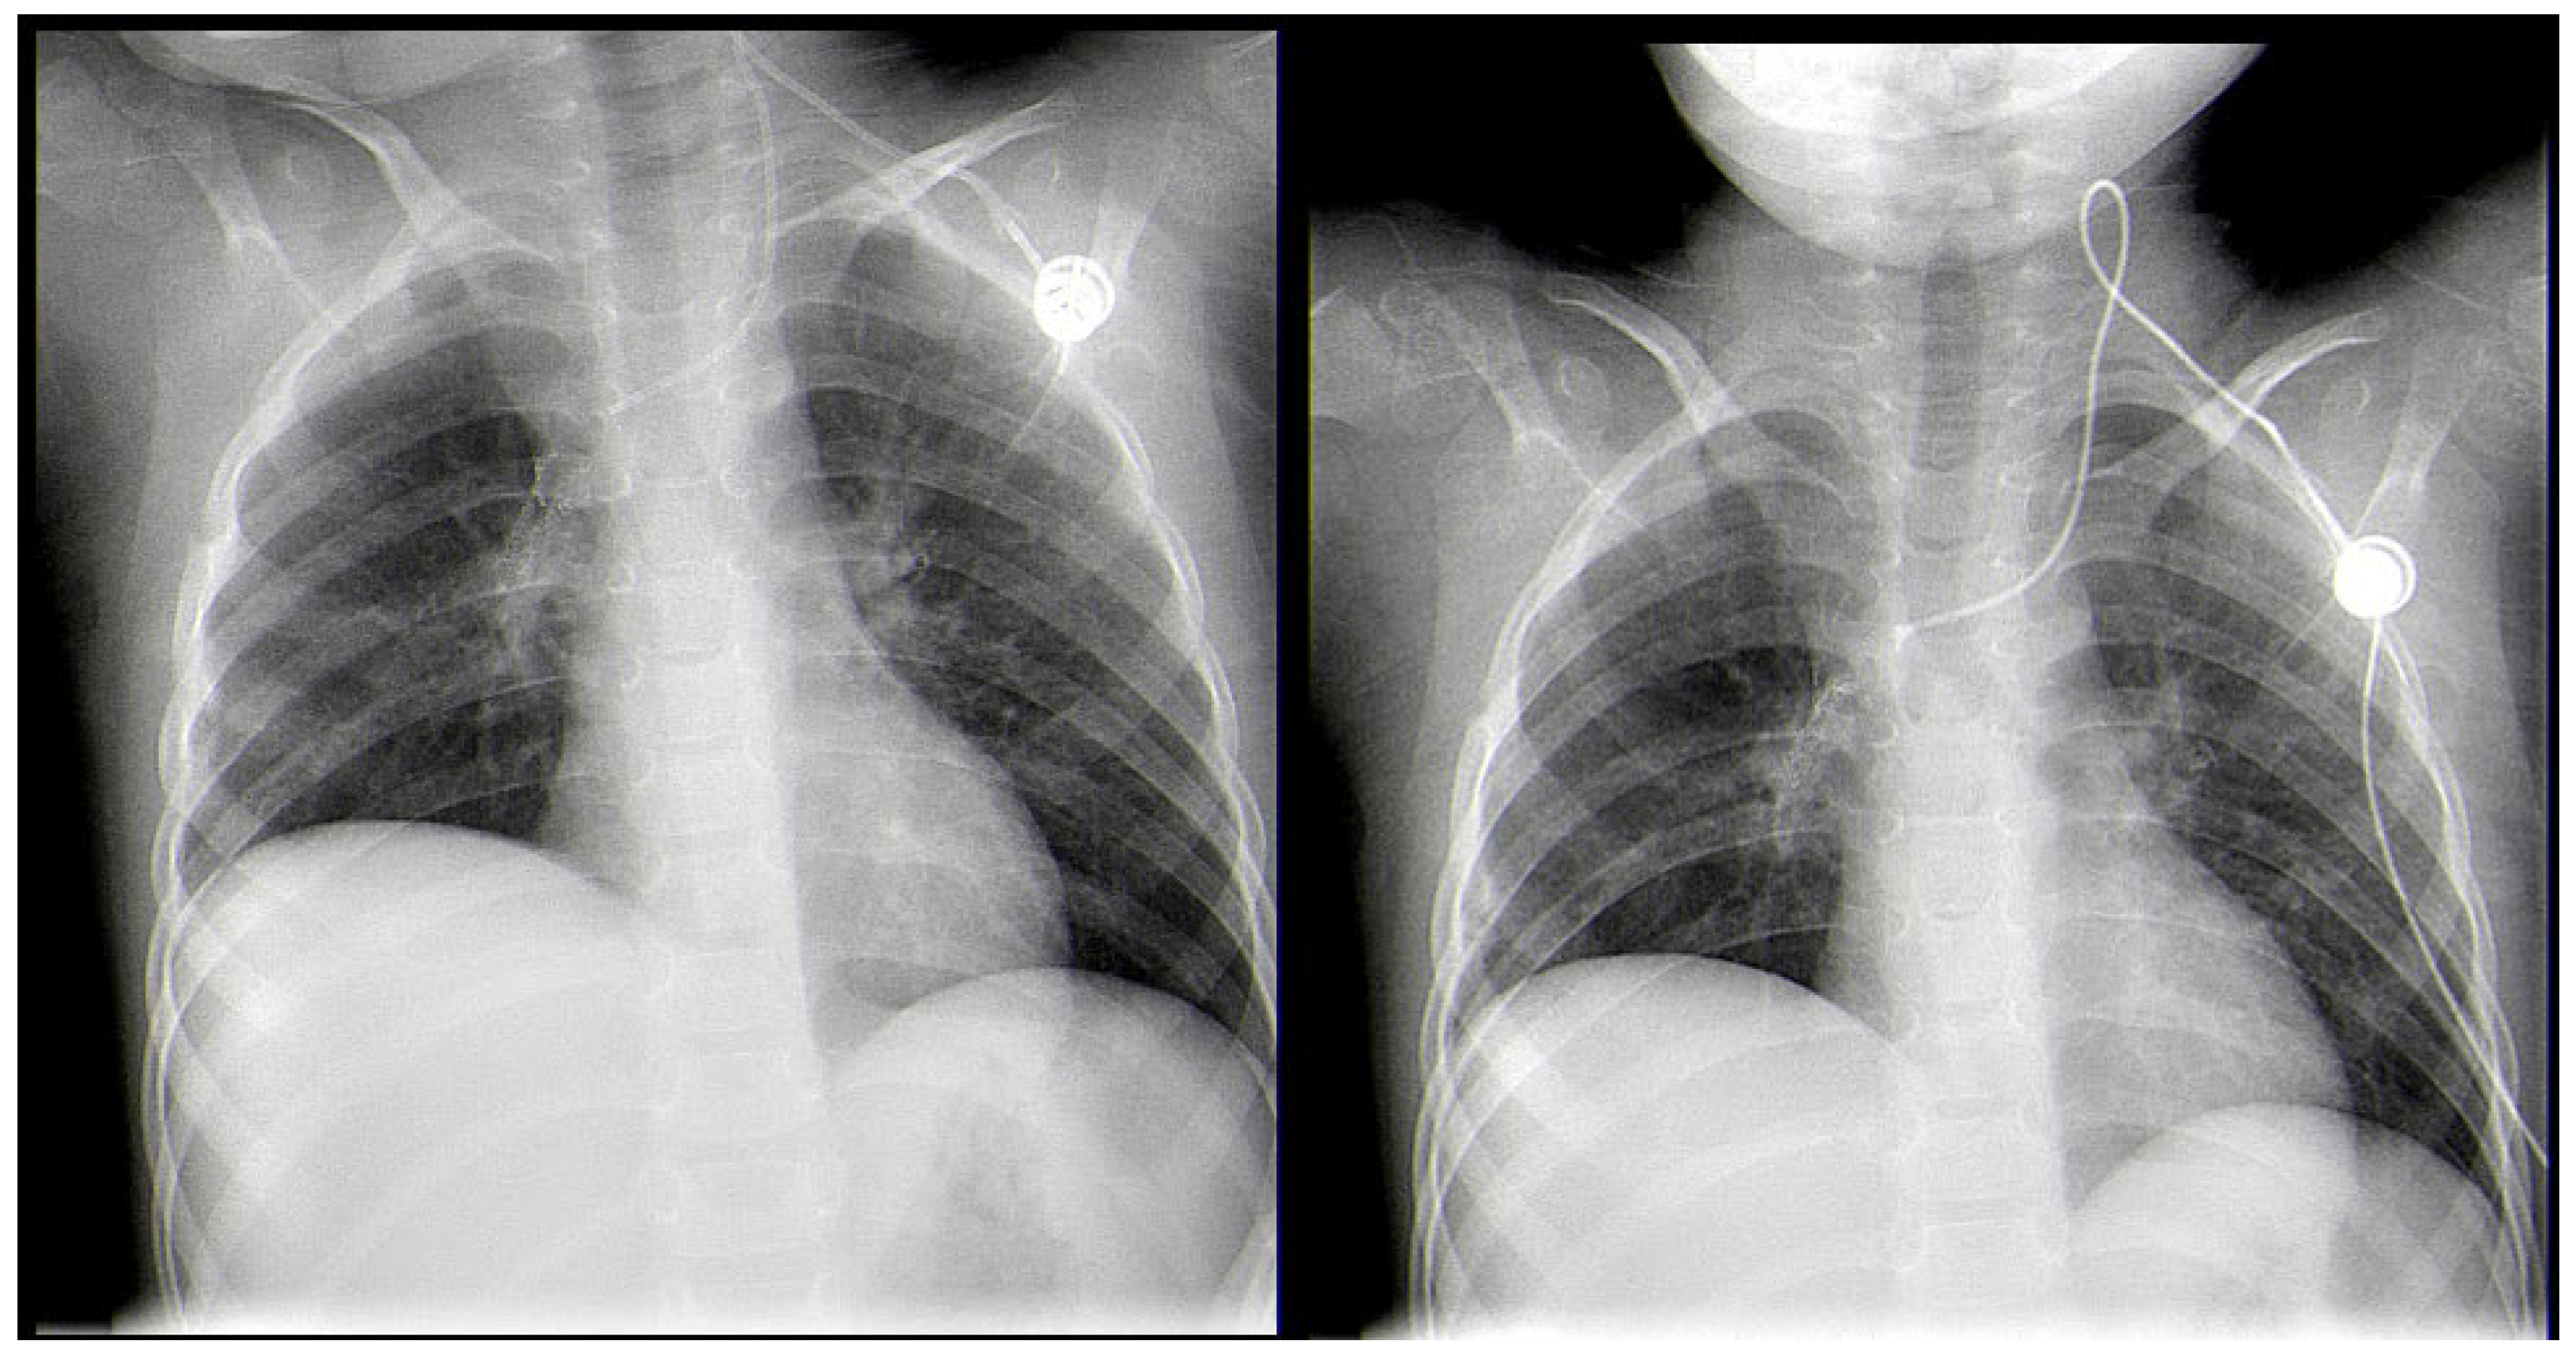

2. Case Report